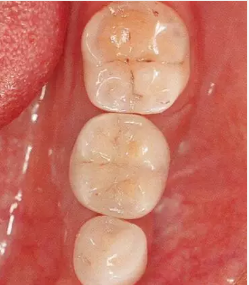

▲圖10-9,10

頰舌側(cè)都獲得了充足的角化齦,菌斑控制狀態(tài)良好。

▲圖10-11,12

佩戴最終修復(fù)體后2年的狀態(tài)。頰舌側(cè)角化齦寬度均充足。